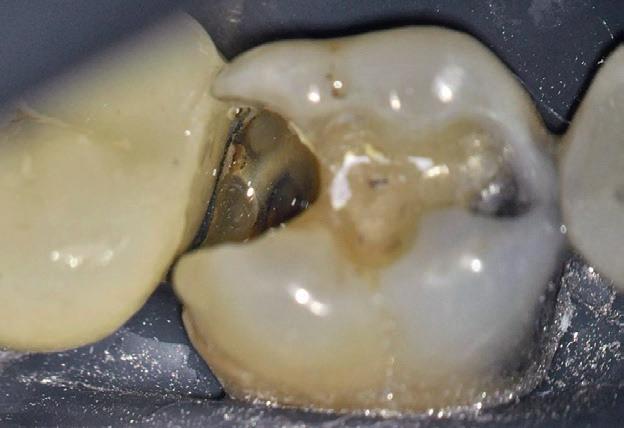

Figurile:

10. Restaurarea Biodentine™ după 2 luni.

11. Îndepărtarea părții externe a Biodentine™.

12. Gravarea selectivă a smalțului.

13. Aplicarea adezivului.

14. Plasarea unui sistem de matrice (Septomatrix, Septodont)

15. Reconstrucția cu compozit a peretelui distal.

16. Restaurarea imediat după finalizare.

17. Situația clinică după finisare și lustruire.